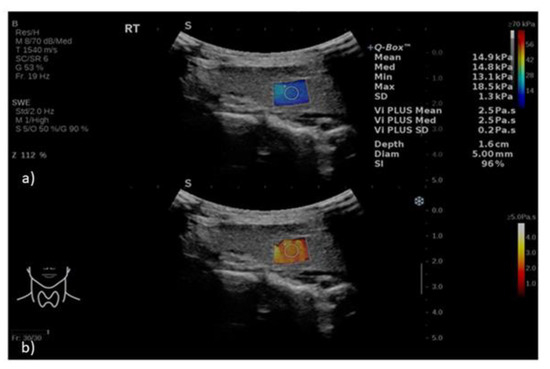

| Right Lobe | Left Lobe | |||

| Viscosity (Pa.s) | Mean | 2.73 | 2.64 | p = 0.525 |

| SD | 1.12 | 0.54 | ||

| 95% CI | 2.48–2.97 | 2.52–2.76 | ||

| SWE (kPa) | Mean | 15.88 | 15.80 | p = 0.911 |

| SD | 4.24 | 5.40 | ||

| 95% CI | 14.95–16.80 | 14.61–16.98 |